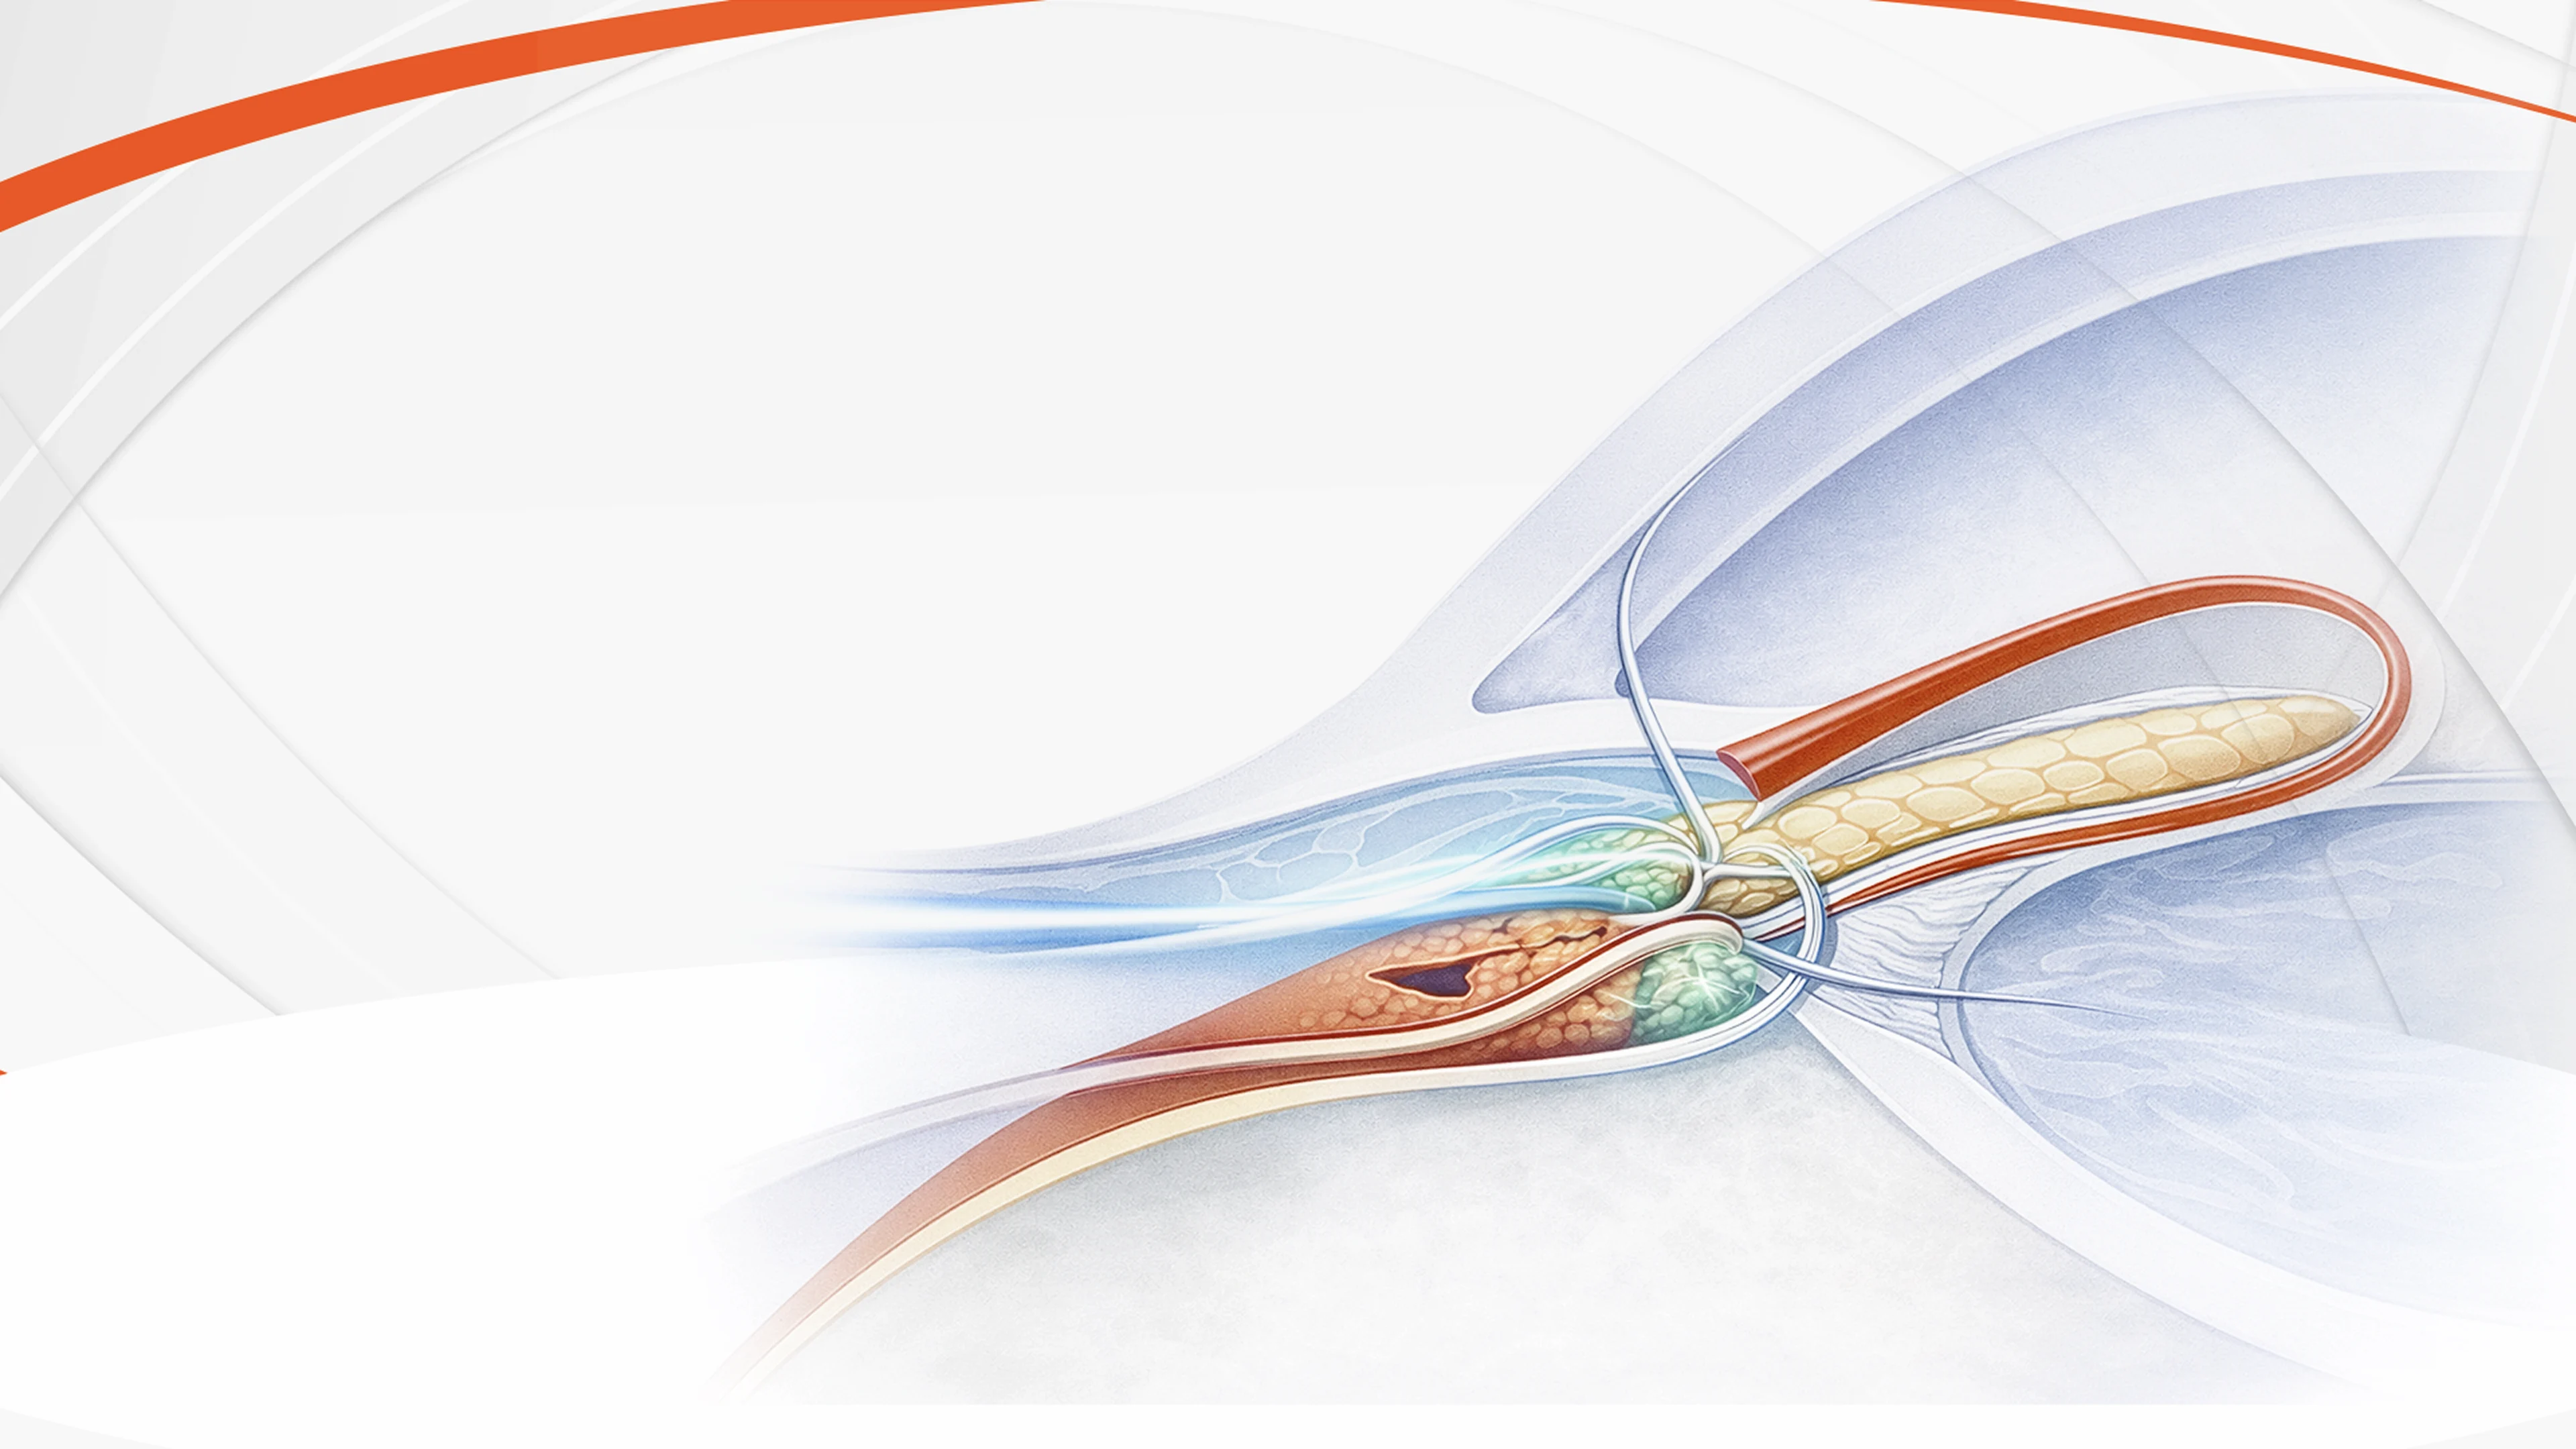

¿Dónde actúa cada tratamiento?

Arrastra cada clase terapéutica

hacia la zona

del ojo donde actúa.

hacia la zona del ojo donde actúa

Análogos de Prostaglandinas

-

Inhibidores de la Rho quinasa

-

b-bloqueadores

-

CAIs

-

Alfa agonistas

ciliares

uveoescleral